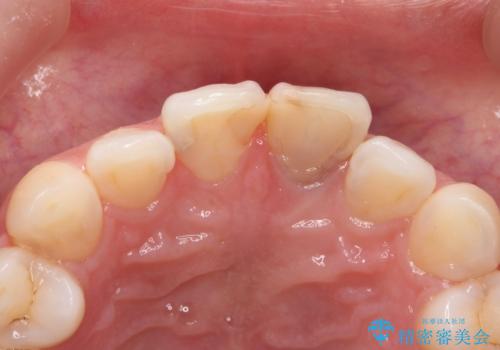

- 前歯部の歯ぐきが腫れたり、にきびのようなものが繰り返しできる。と不快症状を訴えて来院されました。

X線検査を行い診断的な小手術を行ったところ、歯に亀裂があり修復が不可能な状態であることがわかりました。

長期的な予後を見通すことが難しかったので、亀裂のある前歯の抜去を行いブリッジで審美性・機能性の回復を行いました。